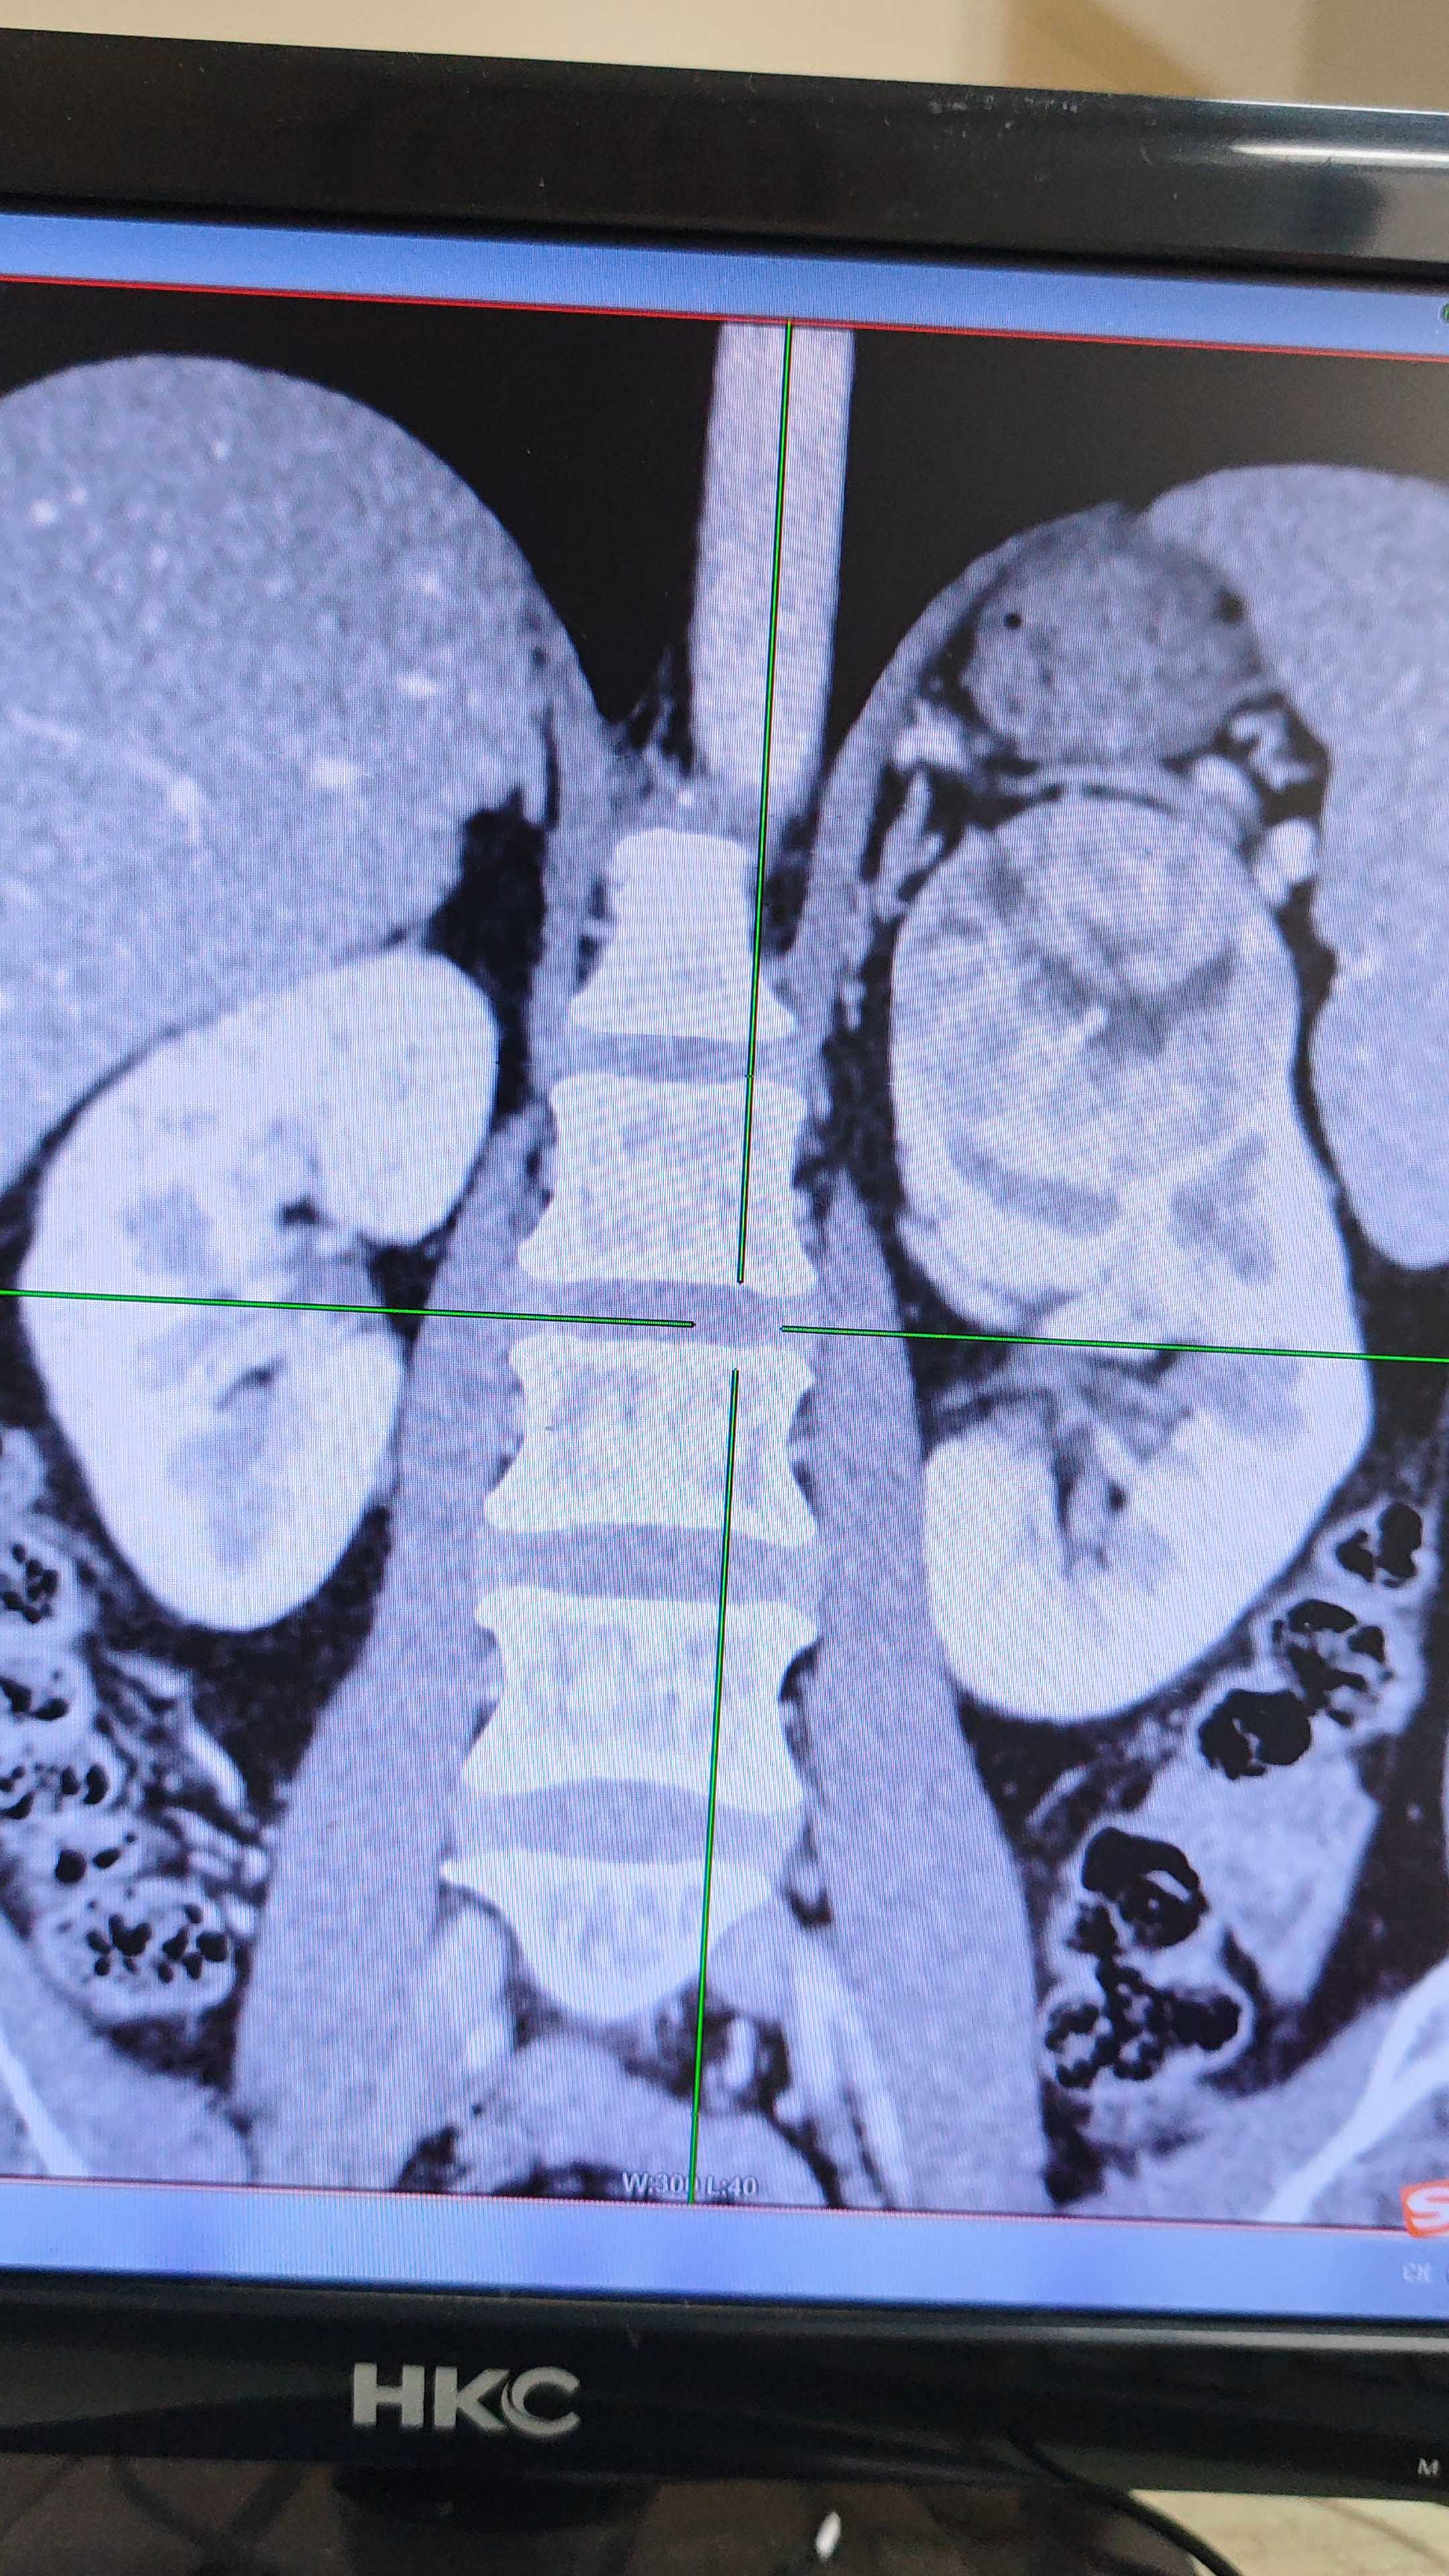

患者,女,43岁,体检发现肾肿瘤3天。

增强CT检查

肾部分切还是根治。